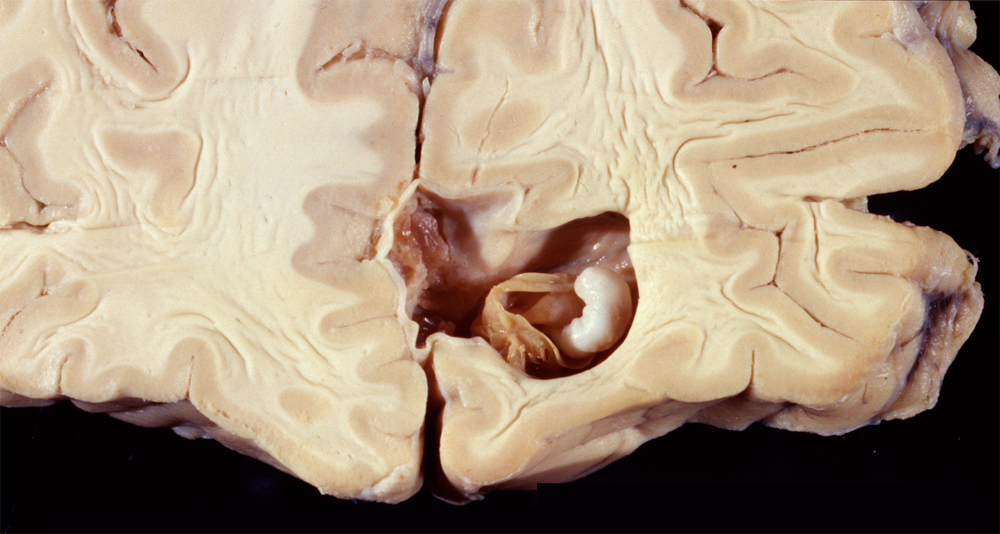

Cryptococcus is an oval yeast about the size of a red cell, surrounded by a gelatinous capsule. There are several species of cryptococcus. The most common, cryptococcus neoformans, causes 95% of infections. It is a worldwide fungus, present in bird droppings, vegetables, and soil. It may affect healthy individuals but is particularly common in immunodeficient patients, especially patients with HIV/AIDS. It is most often community-acquired. The portal of entry is the respiratory tract but pulmonary infection may be asymptomatic or minimally symptomatic. Cryptococcus spreads to the brain from the lungs and often causes meningitis without involving other organs. In the CNS, cryptococcus grows extensively in the subarachnoid space and perivascular spaces, which become cystically distended to the point that brain sections look like Swiss cheese. In immunosuppressed individuals, inflammation is absent or mild. In immunocompetent hosts, cryptococcus elicits a cell-mediated immune reaction with lymphocytes and epithelioid cell granulomas. Rarely cryptococcus may cause mass lesions (cryptococcomas). Cryptococcus meningitis has an insidious onset and may go on from weeks to years. It can cause hydrocephalus, dementia, cranial neuropathies and focal neurological deficits. The CSF in cryptococcosis shows mononuclear pleocytosis, elevated protein, and low glucose, similar to tuberculous meningitis. Yeasts can be identified by microscopy of the CSF and their antigens can be detected by latex agglutination.